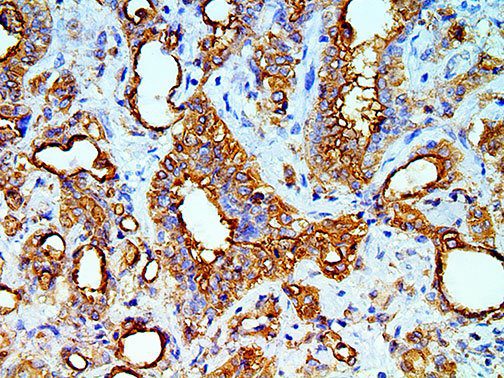

The first cytokines released are interleukin 1β (IL-1β) and tumor necrosis factor-α (TNF-α), which attract a variety of circulating white blood cells (WBCs) to the infection site, including neutrophils, monocytes, macrophages, and natural killer (NK) cells. This response, along with the antipathogenic chemicals released by these cells (i.e., complement), comprise the innate immune response. These cells directly attack the invading pathogen and also release additional cytokines, chief among them interleukin-1 and 6 (IL-6). IL-6 is essential for invoking the adaptive immune response, which calls T-cells, B-cells, and T helper (Th) cells to the infection site. IL-6 also stimulates further recruitment, proliferation and activation of macrophages.

It is the ICU physician who is most likely to witness one of the deadliest manifestations of the abnormal immunological response, the cytokine storm syndrome (CSS). This response is also referred to by some as the cytokine release syndrome (CRS). CSS is characterized by continuous activation and expansion of macrophage and lymphocyte populations, which secrete large amounts of cytokines, causing the cytokine storm. This massive cytokine release is akin to hemophagocytic lymphohistiocytosis (HLH) disease, a syndrome characterized by initial unchecked and persistent activation of cytotoxic T lymphocytes and NK cells.